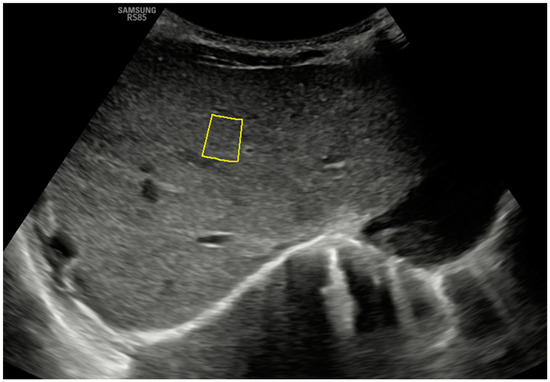

Figure 3.

Ultrasonographic example of a hepatic axial section in segment IV with sample acquisition using 2D-SWE and a linear probe, following the same methodology described in Figure 2.